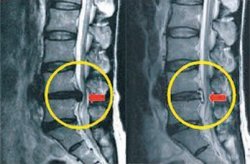

하이브리드 고주파 시술 전후 척추 X레이.